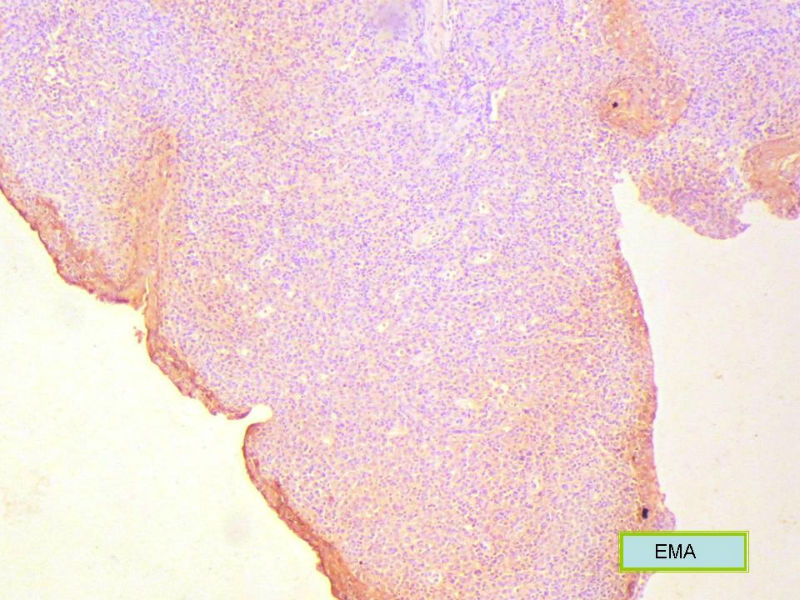

该患者可能存在病毒的感染,抑或是EB病毒的感染,包括CD30+的细胞在内,夹杂在组织细胞、小淋巴细胞之间的一些个大细胞是活化的淋巴细胞,表型看来属B细胞。整个形态呈反应性增生的形态。

总之,现有的图片显示的形态和IHC标记尚不足以诊断为淋巴瘤,除非有有基因重排的支持。

请看下图,显示的细胞比较杂,胞浆较丰富,胞核没有什么特别的异型性。没有促纤维增生反应和围血管生长表现,没有肿瘤性坏死,没有见到更多的核分裂,特别是病理性核分裂。因此认为,本例是淋巴组织反应性增生,可能是对病毒感染的反应。